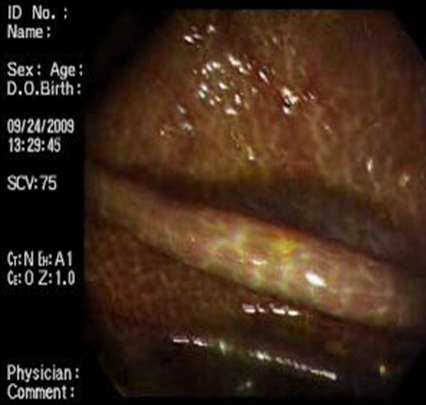

Figura nº 7: Se observa pliegue característico de la región del ciego, en el colon derecho, en esta zona generalmente la melanosis coli se observa con mayor frecuencia.

Figura nº 8: Se observa la coloración café negruzca, más intensa en la región del ciego.